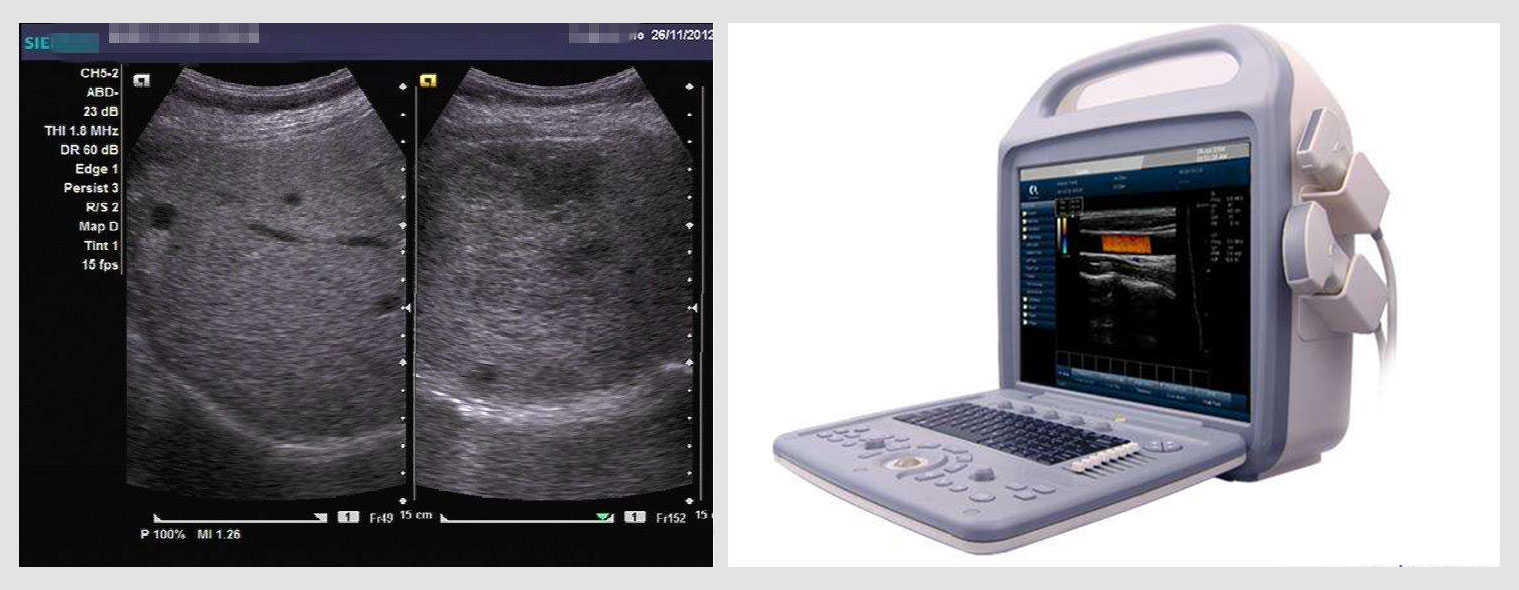

超声定位硬化剂注射,超声定位以后利用穿刺针通过人体皮肤或粘膜将药物灌注入瘤体的治疗方法。能够准确地直接到达病变局部,同时又没有大的创伤,因此具有准确、安全、高效、适应证广、并发症少等优点,现已成为血管瘤及脉管畸形的首选治疗方法。